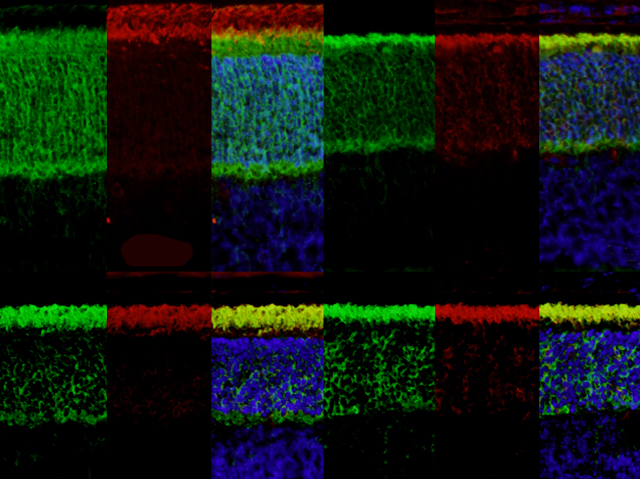

La síndrome de Bardet-Biedl (BBS) és una malaltia complexa. Més de 15 canvis genètics heretats han sigut implicats en aquesta afecció, i afecta a la vista, l’olfacte, el creixement, el comportament i altres. Aquests problemes es resumeixen en defectes en els cilis –xicotets pèls sensorials que podem trobar en la superfície de les cèl·lules. Un lloc amb gran quantitat de cilis és la retina, a la part posterior de l’ull, que detecta la llum, per tant, és d’esperar que la gent amb BBS tinga problemes de visió. Aquestes imatges mostren seccions de la retina de ratolí, amb distintes capes destacades amb diferents colorants. Els 3 panells de dalt a l'esquerra són d’un animal sa, mentre que els altres conjunts d’imatges són d’animals amb canvis genètics relacionats amb la BBS, que no han format correctament les capes de la retina. Resolent quina cosa funciona incorrectament a aquestes cèl·lules, els investigadors esperen trobar noves pistes per entendre la BBS i desenvolupar maneres de salvar la visió dels pacients.